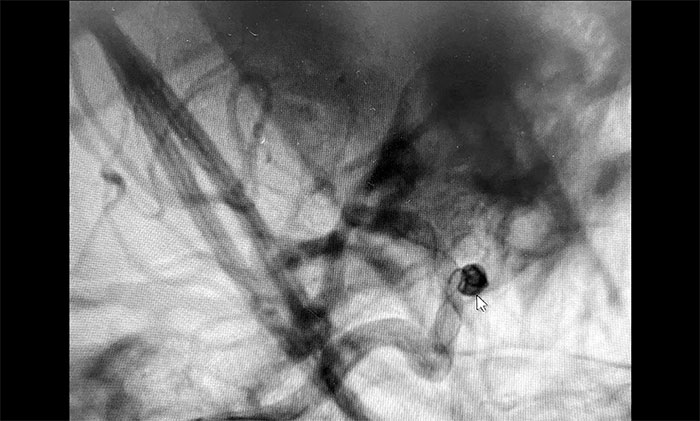

▲動脈瘤栓塞

在排除明顯手術(shù)禁忌,告知患者家屬手術(shù)風(fēng)險并獲得同意后,神經(jīng)外科6A病區(qū)醫(yī)生團(tuán)隊(duì)為秦女士開展了顱內(nèi)動脈瘤栓塞手術(shù)。

術(shù)中,在微導(dǎo)絲的引導(dǎo)下將微導(dǎo)管頭端小心送入動脈瘤腔內(nèi),之后順著這個通路往動脈瘤內(nèi)填塞彈簧圈,造影顯示動脈瘤瘤內(nèi)造影劑明顯滯留,眼動脈(載瘤動脈)血流通暢。遂解脫彈簧圈并釋放支架,再次造影,支架覆蓋動脈瘤,貼壁良好。整臺手術(shù)歷時90分鐘順利完成,患者術(shù)后恢復(fù)情況良好。